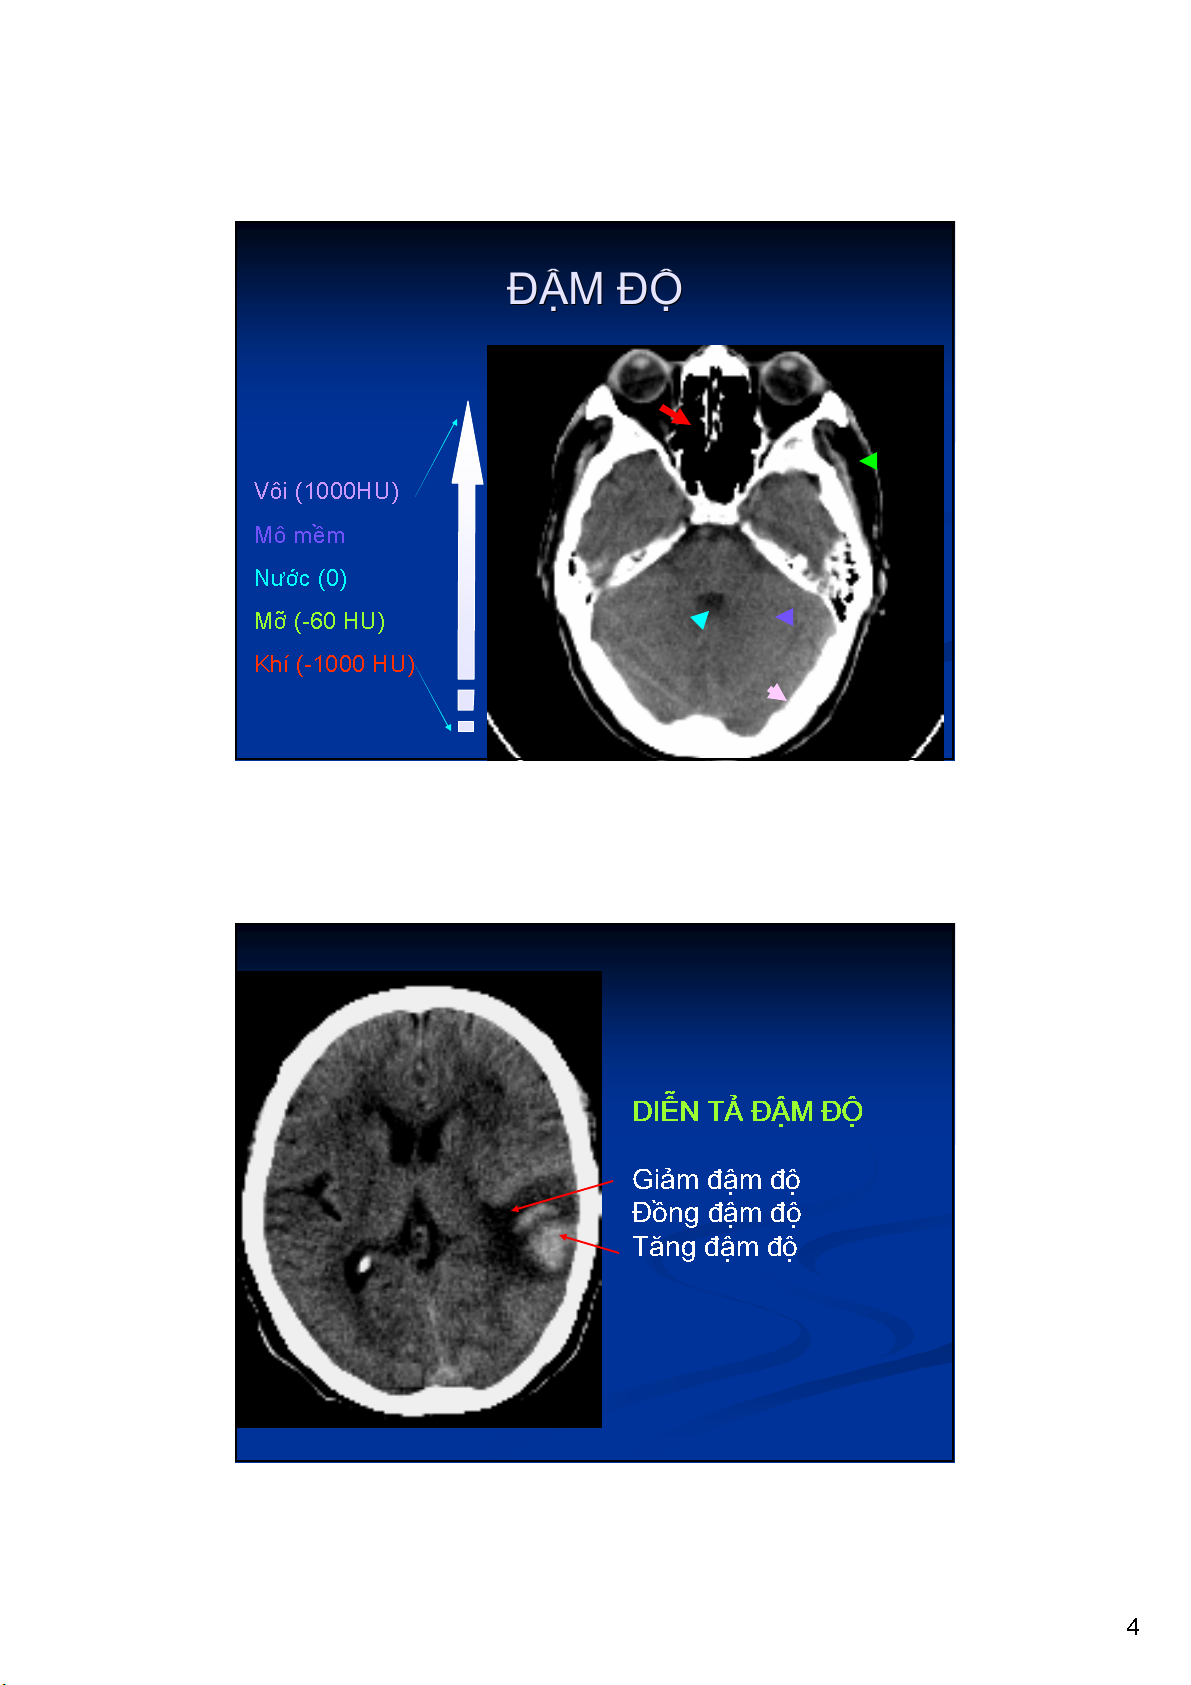

Vôi (1000HU)

Mô mềm

Nước (0)

Mỡ (-60 HU)

Khí (-1000 HU)

Giảm đậm độ

Đồng đậm độ

Tăng đậm độ